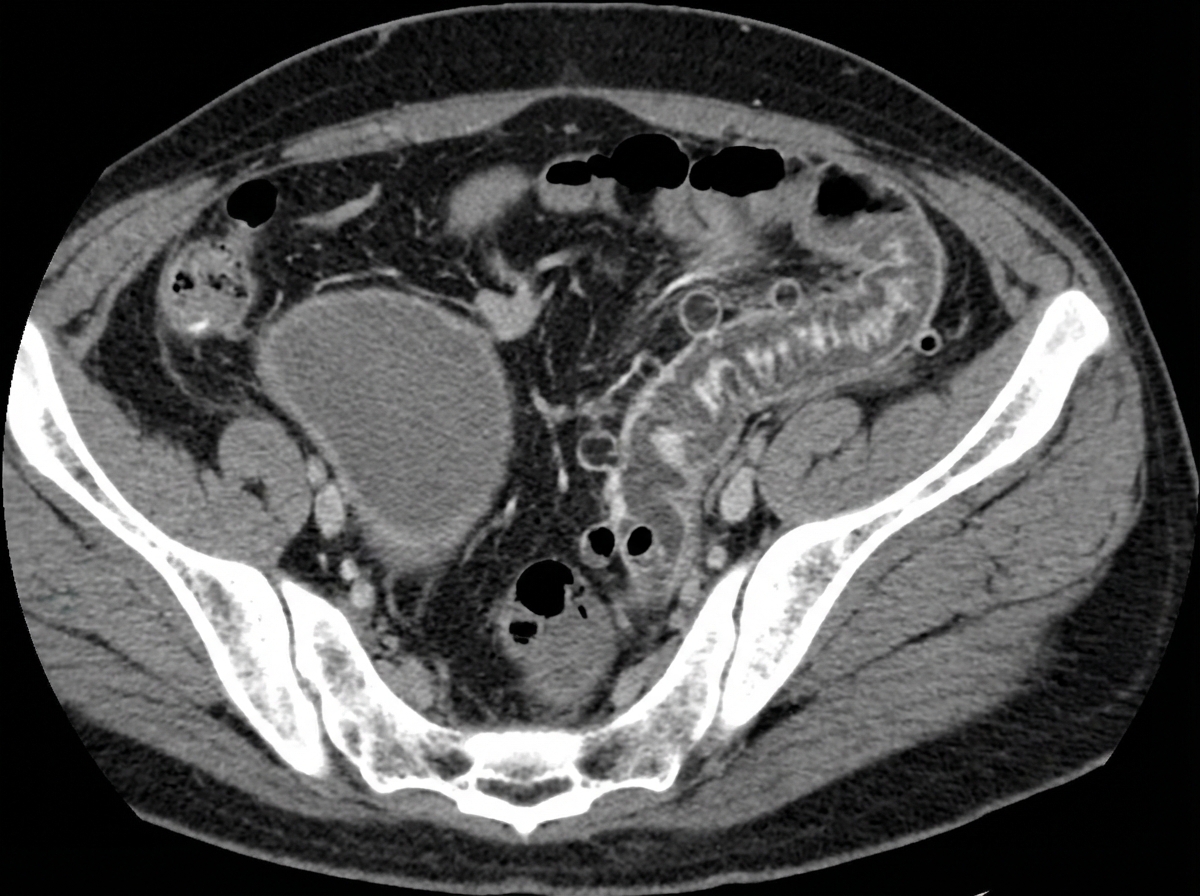

A 55-year-old woman comes to the emergency department because of a 24-hour history of severe lower abdominal pain. She has had two episodes of nonbloody vomiting today and has been unable to keep down food or fluids. She has not had a bowel movement since the day before. She has hypertension, hyperlipidemia, and osteoarthritis. She had a cholecystectomy 5 years ago. She has smoked one pack of cigarettes daily for the last 20 years. Current medications include chlorthalidone, atorvastatin, and naproxen. Her temperature is 38.8°C (101.8°F), pulse is 102/min, respirations are 20/min, and blood pressure is 118/78 mm Hg. She is 1.68 m (5 ft 6 in) tall and weighs 94.3 kg (207.9 lbs); BMI is 33.4 kg/m2. Abdominal examination shows a soft abdomen with hypoactive bowel sounds. There is moderate left lower quadrant tenderness. A tender mass is palpable on digital rectal examination. There is no guarding or rebound tenderness. Laboratory studies show: Leukocyte count 17,000/mm3 Hemoglobin 13.3 g/dl Hematocrit 40% Platelet count 188,000/mm3 Serum Na+ 138 mEq/L K+ 4.1 mEq/L Cl- 101 mEq/L HCO3- 22 mEq/L Urea Nitrogen 18.1 mg/dl Creatinine 1.1 mg/dl Which of the following is most appropriate to confirm the diagnosis?

A 67-year-old man comes to the emergency department complaining of severe abdominal pain for the last several hours. The pain is cramp-like in nature, constant, 8/10, and has worsened over time. It is associated with bilious vomiting. He gives a history of episodic right upper abdominal pain for the past few months, mostly after consuming fatty foods, radiating to the tip of the right scapula. He reports no change in bowel habits, bladder habits, or change in weight. His past medical history includes diabetes and hypertension, and he takes hydrochlorothiazide, metformin, ramipril, and atorvastatin. Temperature is 38.2°C (100.8°F), blood pressure is 110/70 mm Hg, pulse is 102/min, respiratory rate is 20/min, and BMI is 23 kg/m2. On physical examination, his abdomen is distended and diffusely tender. Laboratory test Complete blood count Hemoglobin 13 g/dL WBC 16,000/mm3 Platelets 150,000/mm3 Basic metabolic panel Serum Na+ 148 mEq/L Serum K+ 3.3 mEq/L Serum Cl- 89 mEq/L An abdominal CT scan is shown. What is the most likely underlying cause of this patient’s current presentation?